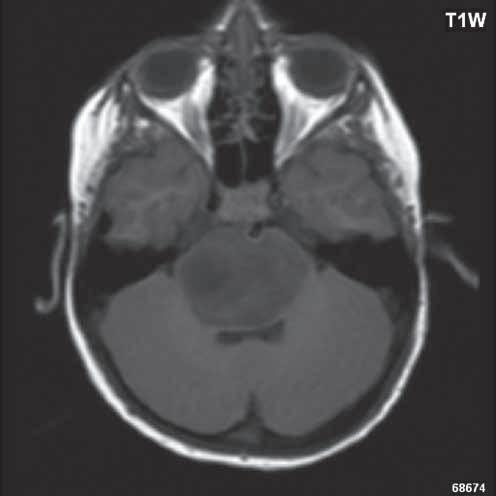

Zobrazení

D-W malformace je charakterizována hypoplazií vermis mozečku, rozšířením IV. mozkové komory, která se často cysticky vyklenuje dorzálně a může imitovat arachnoidální cystu, rozšířením zadní jámy lební a vysokým úponem tentoria s confluens sinum nad lambdovým švem. Okcipitální kost může být vlivem tlakových změn remodelována, existují i případy s porušením její kontinuity a encefalokélou. Hydrocefalus pozorujeme v 80 %, častá je přítomnost dysgeneze corpus callosum, schizencefalie.

Obr. I.1.8a Dandy-Walkerova malformace, rozšířená IV komora (tvar klíčové dírky)

Obr. I.1.8b Dandy-Walkerova malformace, rozšířená IV komora široce komunikující s cisterna magna, hypotrofie mozečku (snímky zapůjčeny z archivu prim doc MUDr M Mechla, Ph D, MBA)

Obr. I.1.8c Dandy-Walkerova malformace, rozšířená IV komora široce komunikující s cisterna magna, hypotrofie mozečku (snímky zapůjčeny z archivu prim doc MUDr M Mechla, Ph D, MBA); stejný pacient jako na obr I 1 8b

Obr. I.1.8d Dandy-Walkerova malformace, rozšířená IV komora široce komunikující s cisterna magna, hypotrofie mozečku, vysoký úpon tentoria (šipka) (snímky zapůjčeny z archivu prim doc MUDr M Mechla, Ph D, MBA); stejný pacient jako na obr I 1 8b, c